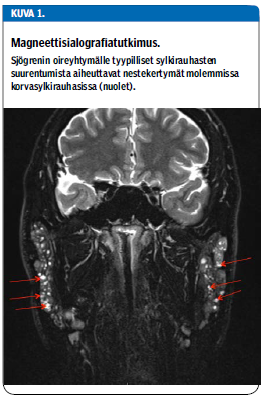

Sylkirauhasten kaikututkimusta käytetään yhä enemmän apuna Sjögrenin oireyhtymän diagnostiikassa, vaikka se ei kuulukaan sairauden luokittelukriteereihin. Oireyhtymää sairastavalla voidaan todeta sylkirauhasten atrofioitumista tai epähomogeenisyyttä. Erityisesti sylkirauhaskasvainta epäiltäessä tarkempia tutkimuksia ovat MRI ja magneettisialografia (kuva 1 «»4) (4).

Kiitokset korva-, nenä- ja kurkkutautien erikoislääkäri Saara Sillanpäälle sylkirauhasen magneettisialografiakuvasta (kuva 1).